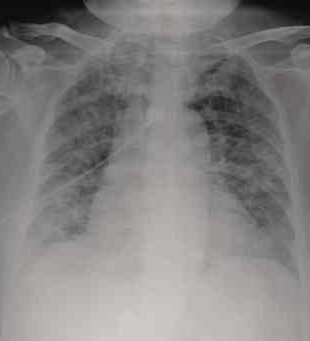

好奇怪,怎么回事,昨天晚上一个人在家睡觉,起床后,周围全都是血,我床上好多,我家小狗一直在看我,不出声,起来后好奇怪。吓死我了,那里的血,检查自己,没有伤口,上午去一趟医院全面检查没问题,还有我家都锁这门,没有人进来,在说我家住9楼,我是男的,这怎么回事,帮帮我,起来就是胸口特别疼,但是没有刀痕问题  这个是胸部的

这不是一个人的片子吧。。第二张现实你肺气肿伴重度心脏肥大,赶紧住院吧,就你这情况分分钟心衰猝死